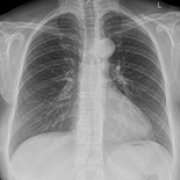

14 Nov 2021 : Clinical Research

Clinical Features and Temporal Lung Radiographic Changes in 25 Patients Recovering from COVID-19 Pneumonia: A Retrospective Case-Control Study

Chao Hu, Jian Ping Zeng, Ke Peng, Hong Xia, Huan Ming Zhang, Zhi Zhong, Ming Yan Jiang

DOI: 10.12659/MSM.933381

Med Sci Monit 2021; 27:e933381

3,640 973 0

3640 973 0